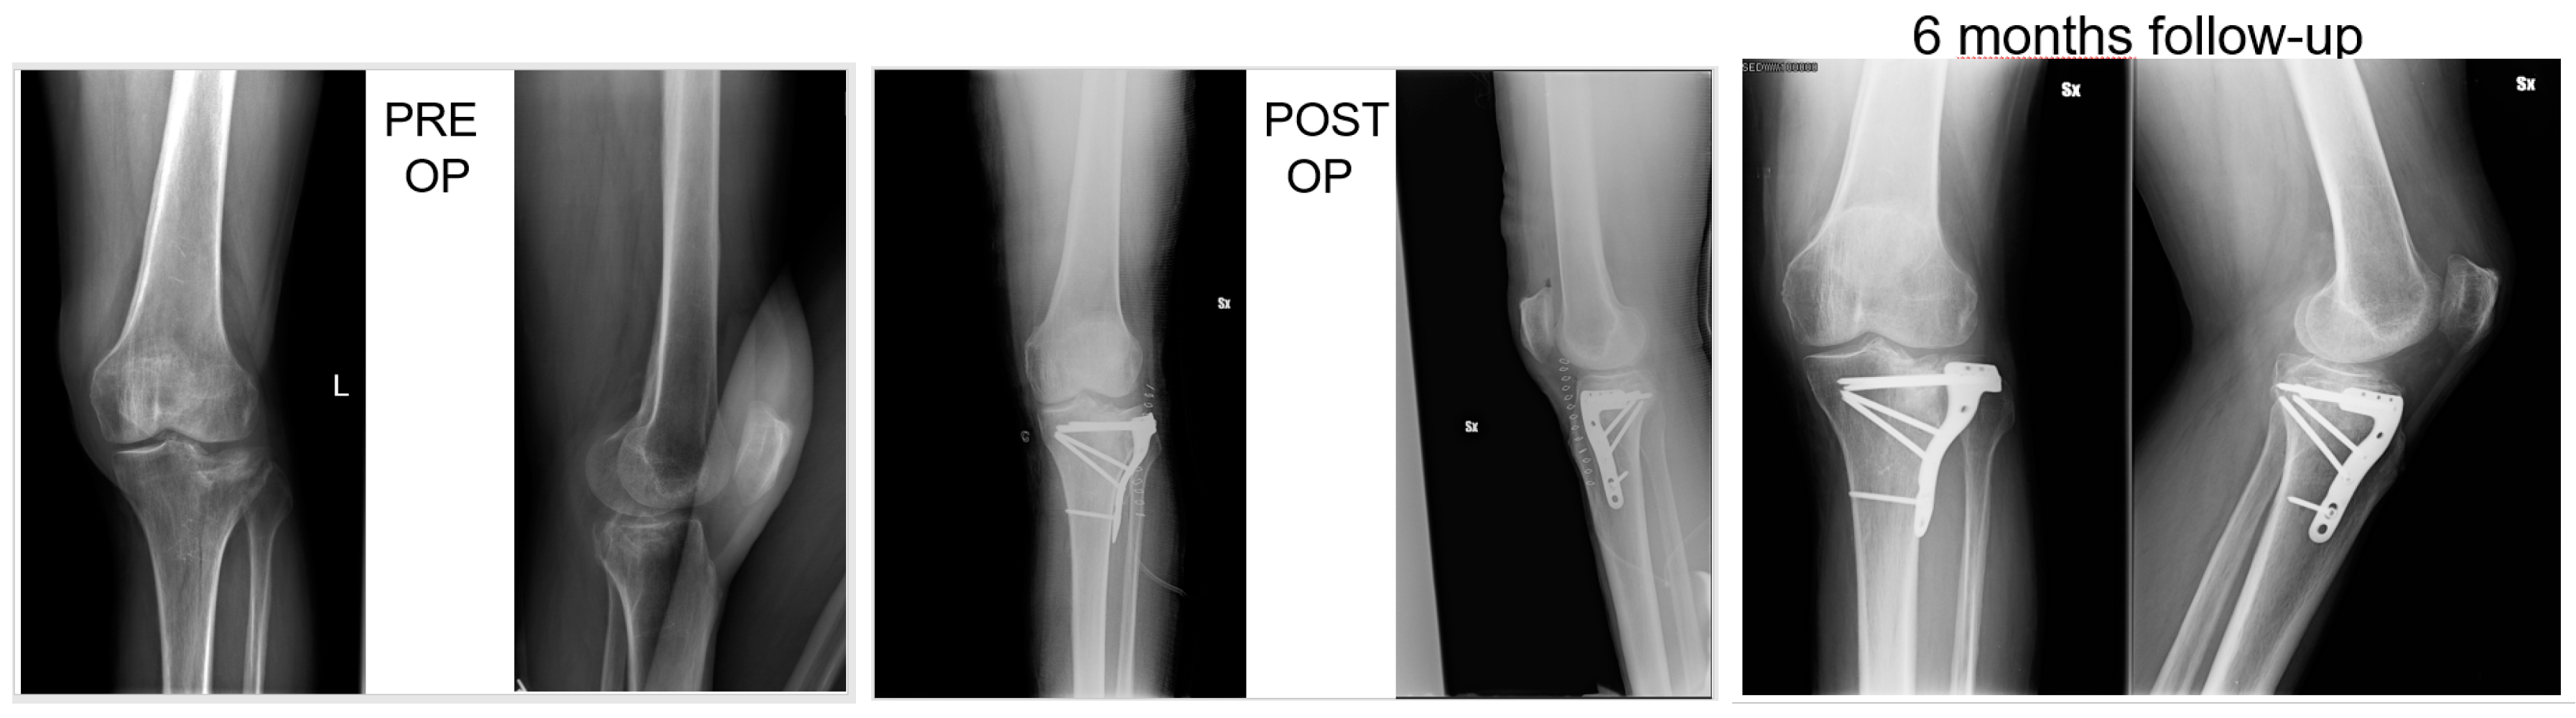

Figure 1. Fifty-seven-year-old patient, X-rays: preoperative, postoperative and control at 6 months follow up of a Shatzker type 2 fracture, AO 41 B1.3.

All patients had surgery within 48 hours from injury, after administration of spinal or general anaesthesia. A tourniquet was routinely positioned before starting surgical procedure; all patients were operated in a supine position, with injured leg in semi-flexion. Fractures were reduced through a percutaneous or open approach, depending on the cases; SB blocks, which size and shape were customised during surgery considering the features of bone defect for each singular patient, were positioned through a minimally invasive approach via the bony window exploited for reduction; finally, fixation of fracture line and implant were performed with screws and plates (see exemplificative Figure 1, Figure 2 and Figure 3). In one case fixation of the plateau fracture occurred through an arthroscopic approach. All the patients included in the study had identical post-operative regimen. Active knee mobilization and static quadriceps exercises were encouraged from the third day after surgery. Partial weight bearing was allowed at 4–6 weeks after surgery, and progressively increased to achieve full weight bearing at 12 weeks. Prophylaxis for thromboembolic events was obtained through administration of 4000 IU/day of low molecular weight heparin (LMWH) (enoxaparin), until full weight bearing was allowed.

Patients were clinically and radiologically assessed before surgery, at 2 weeks, and then at 1, 2, and 6 months, and 1 year after surgery. Same radiologist carried out the imaging, while evaluations were pooled by different clinicians. Clinical assessment consisted of a visual analogue scale (VAS) for the evaluation of pain, where patients were asked to report the level of pain during the day life activities; measurement of the range of motion (ROM) of the knee joint; and objective examination, intended to highlight possible alterations of surgical scar, vascular and nervous deficits, as well as infectious complications. Moreover, at 1-year follow-up Tegner Lysholm Knee Scoring Scale [21] and International Knee Document Committee 2000 (IKDC 2000) [22] questionnaires were administered during control visits, in order to evaluate patients’ subjective perception of knee function. One year after surgery, patients answered to the Short Form (36) Health Survey (SF-36) questionnaire, which scores the general physical and mental health on the basis of eight scales each ranging from 0 to 100 [23]. Radiological assessment contemplated the acquisition of anteroposterior and lateral projections radiographs at each follow-up. Images were examined in order to evaluate various features of healing process, like callus formation and maintenance of fracture reduction; as well as to detect the presence of possible malalignment, pseudo-arthrosis, bone non-unions, and articular surface depression or widening (see exemplificative Figure 1, Figure 2 and Figure 3).

At six months, X-rays images showed that all 34 fractures displayed a good consolidation rate, as confirmed by radiological reports. In particular, radiolucency of the xenografts was assessed [20], which became progressively more similar to that of the surrounding healthy bone tissue (see exemplificative Figure 1, Figure 2 and Figure 3 and comparative images in Figure 4).

Comparison with the current literature is challenging, due to the lack of standardised follow-up protocols and differences in quantitative assessment of outcomes among the studies. However, the implant of SB in our series resulted in a standard return to knee mobilisation, as highlighted by the mean ROM at last follow-up and the return to partial weight bearing at 4–6 weeks. We also described no complications, like infections and joint subsidence, if compared to similar studies present in the medical literature [31]. Radiological follow-up did not show diastasis or depressions of tibial articular surface excluding the incomplete subchondral reductions documented at the first post op X-ray, which means that mechanical properties of SB were adequate for high and complex forces which the plateau commonly undergoes. At each follow-up, the radiolucency of implants was progressively more similar to radiolucency of the surrounding bone (see exemplificative Figure 1 and Figure 2). We interpreted this evidence as supporting the thesis that SB would have been able to integrate with autologous bone tissue, favouring deposition of new bone matrix within an ongoing remodelling process: indeed, there is a clear morphological pattern on the evolution of the standard X-Ray imaging series over time which shows the substitution of the grafted material with a more homogeneous signal in the area of graft implant. As already demonstrated, the progressive remodelling together with an increase of the mineral signal cannot be dependent on the active remodelling of the graft per se given it is a decellularized matrix. Therefore, the increase in the density over time depends on novel mineral matrix apposition likely induced by the graft, as previously shown both in vivo and in vitro [7,20].